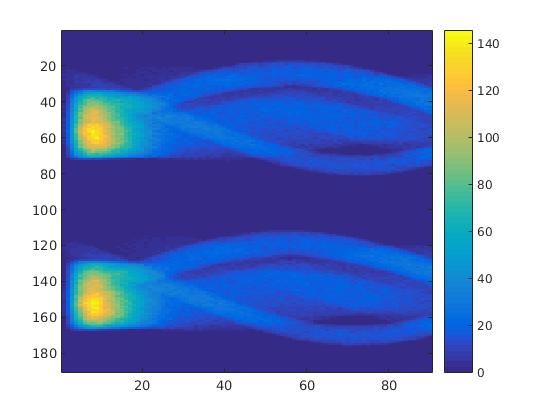

To simulate the synthesized SPECT data, we apply a Radon transform assuming a double detector gamma camera, which counts photons from two opposing projection angles per time step. For the more simple data set, we let the camera rotate clockwise around two degree per time step, in case of the complex data set we used modified projection angles, i.e. the camera alternatingly projects from an angle of i and 45+i degrees, in order to simplify the reconstruction. Each collimator consists of detector bins, so we obtain data points per time step and projection angle. The resulting sinogram data of the two underlying data sets are shown in figure 3.

In a first test, every image sequence was reconstructed out of the exact given sinograms. Additionally we tested noise corrupted data by first scaling the sinogram by a parameter , corrupting them with Poisson noise via the MATLAB imaging toolbox command imnoise and finally rescaling the image to the original range (see figure 4). The average count number per time step (i.e. the average of the discrete -norm of the data at each time step) is approximately in case of the heart-shaped data set and ca. in case of the rat liver simulation. The results at a certain number of time steps can be seen in figure 6 and 7. For comparison, we additionally performed a reconstruction with a simple alternating EM method, keeping the assumption that the tracer can be modelled as a sum of indicator functions and subconcentration curves, but neglecting any regularization terms. In all tests, the outer iteration number was set to 1000 with 10000 inner iterations per subproblem, to obtain a result within a reasonable time period. As stopping criterion, we chose the primal dual residual (cp. [12]) for the inner and the maximum over the Frobenius norms of and for the outer iterations. The results are displayed in 6 and 7 respectively.

As one can see in both figures, the reconstruction method applied to each data set performs very well, especially in contrast to the simple alternating EM method. This clearly shows the benefits of the proposed regularization methods. In case of noise-free given data, the shape of every object, where especially the heart is of higher interest, is clearly defined. As expected, we often observe errors in the edges of each region and where two regions are directly connected (the heart and the upper left circle). This causes the algorithm to incorrectly assign these pixels to another region. Furthermore, the reconstruction difficulties increase with an increase in noise. Some more pixels are assigned to the wrong region, which leads to a small hole-like structure within the heart region and causes a slight blurring effect. In the second data set the method clearly outperforms several other approaches by providing very clearly defined regions and even reconstructing fine structures of the phantom. However, as mentioned before, a clear reconstruction of the rat liver required highly optimized parameter sets, which makes the whole problem quite susceptible to parameter changes.